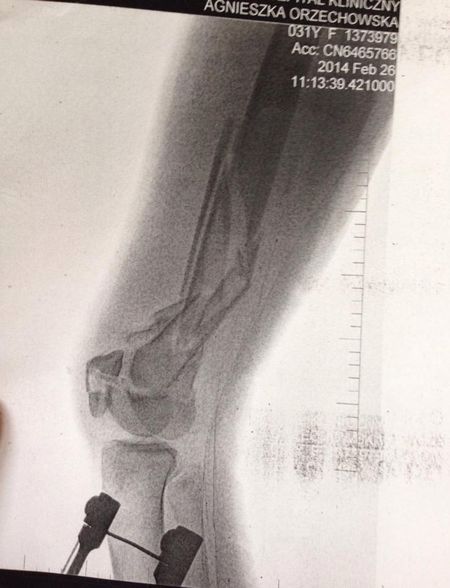

Orzechowska ma połamane obie nogi.

Otarłam się o śmierć. Mam gwóźdź w kolanie. Pierwszy raz byłam w śpiączce - napisała na swoim profilu na Facebooku.